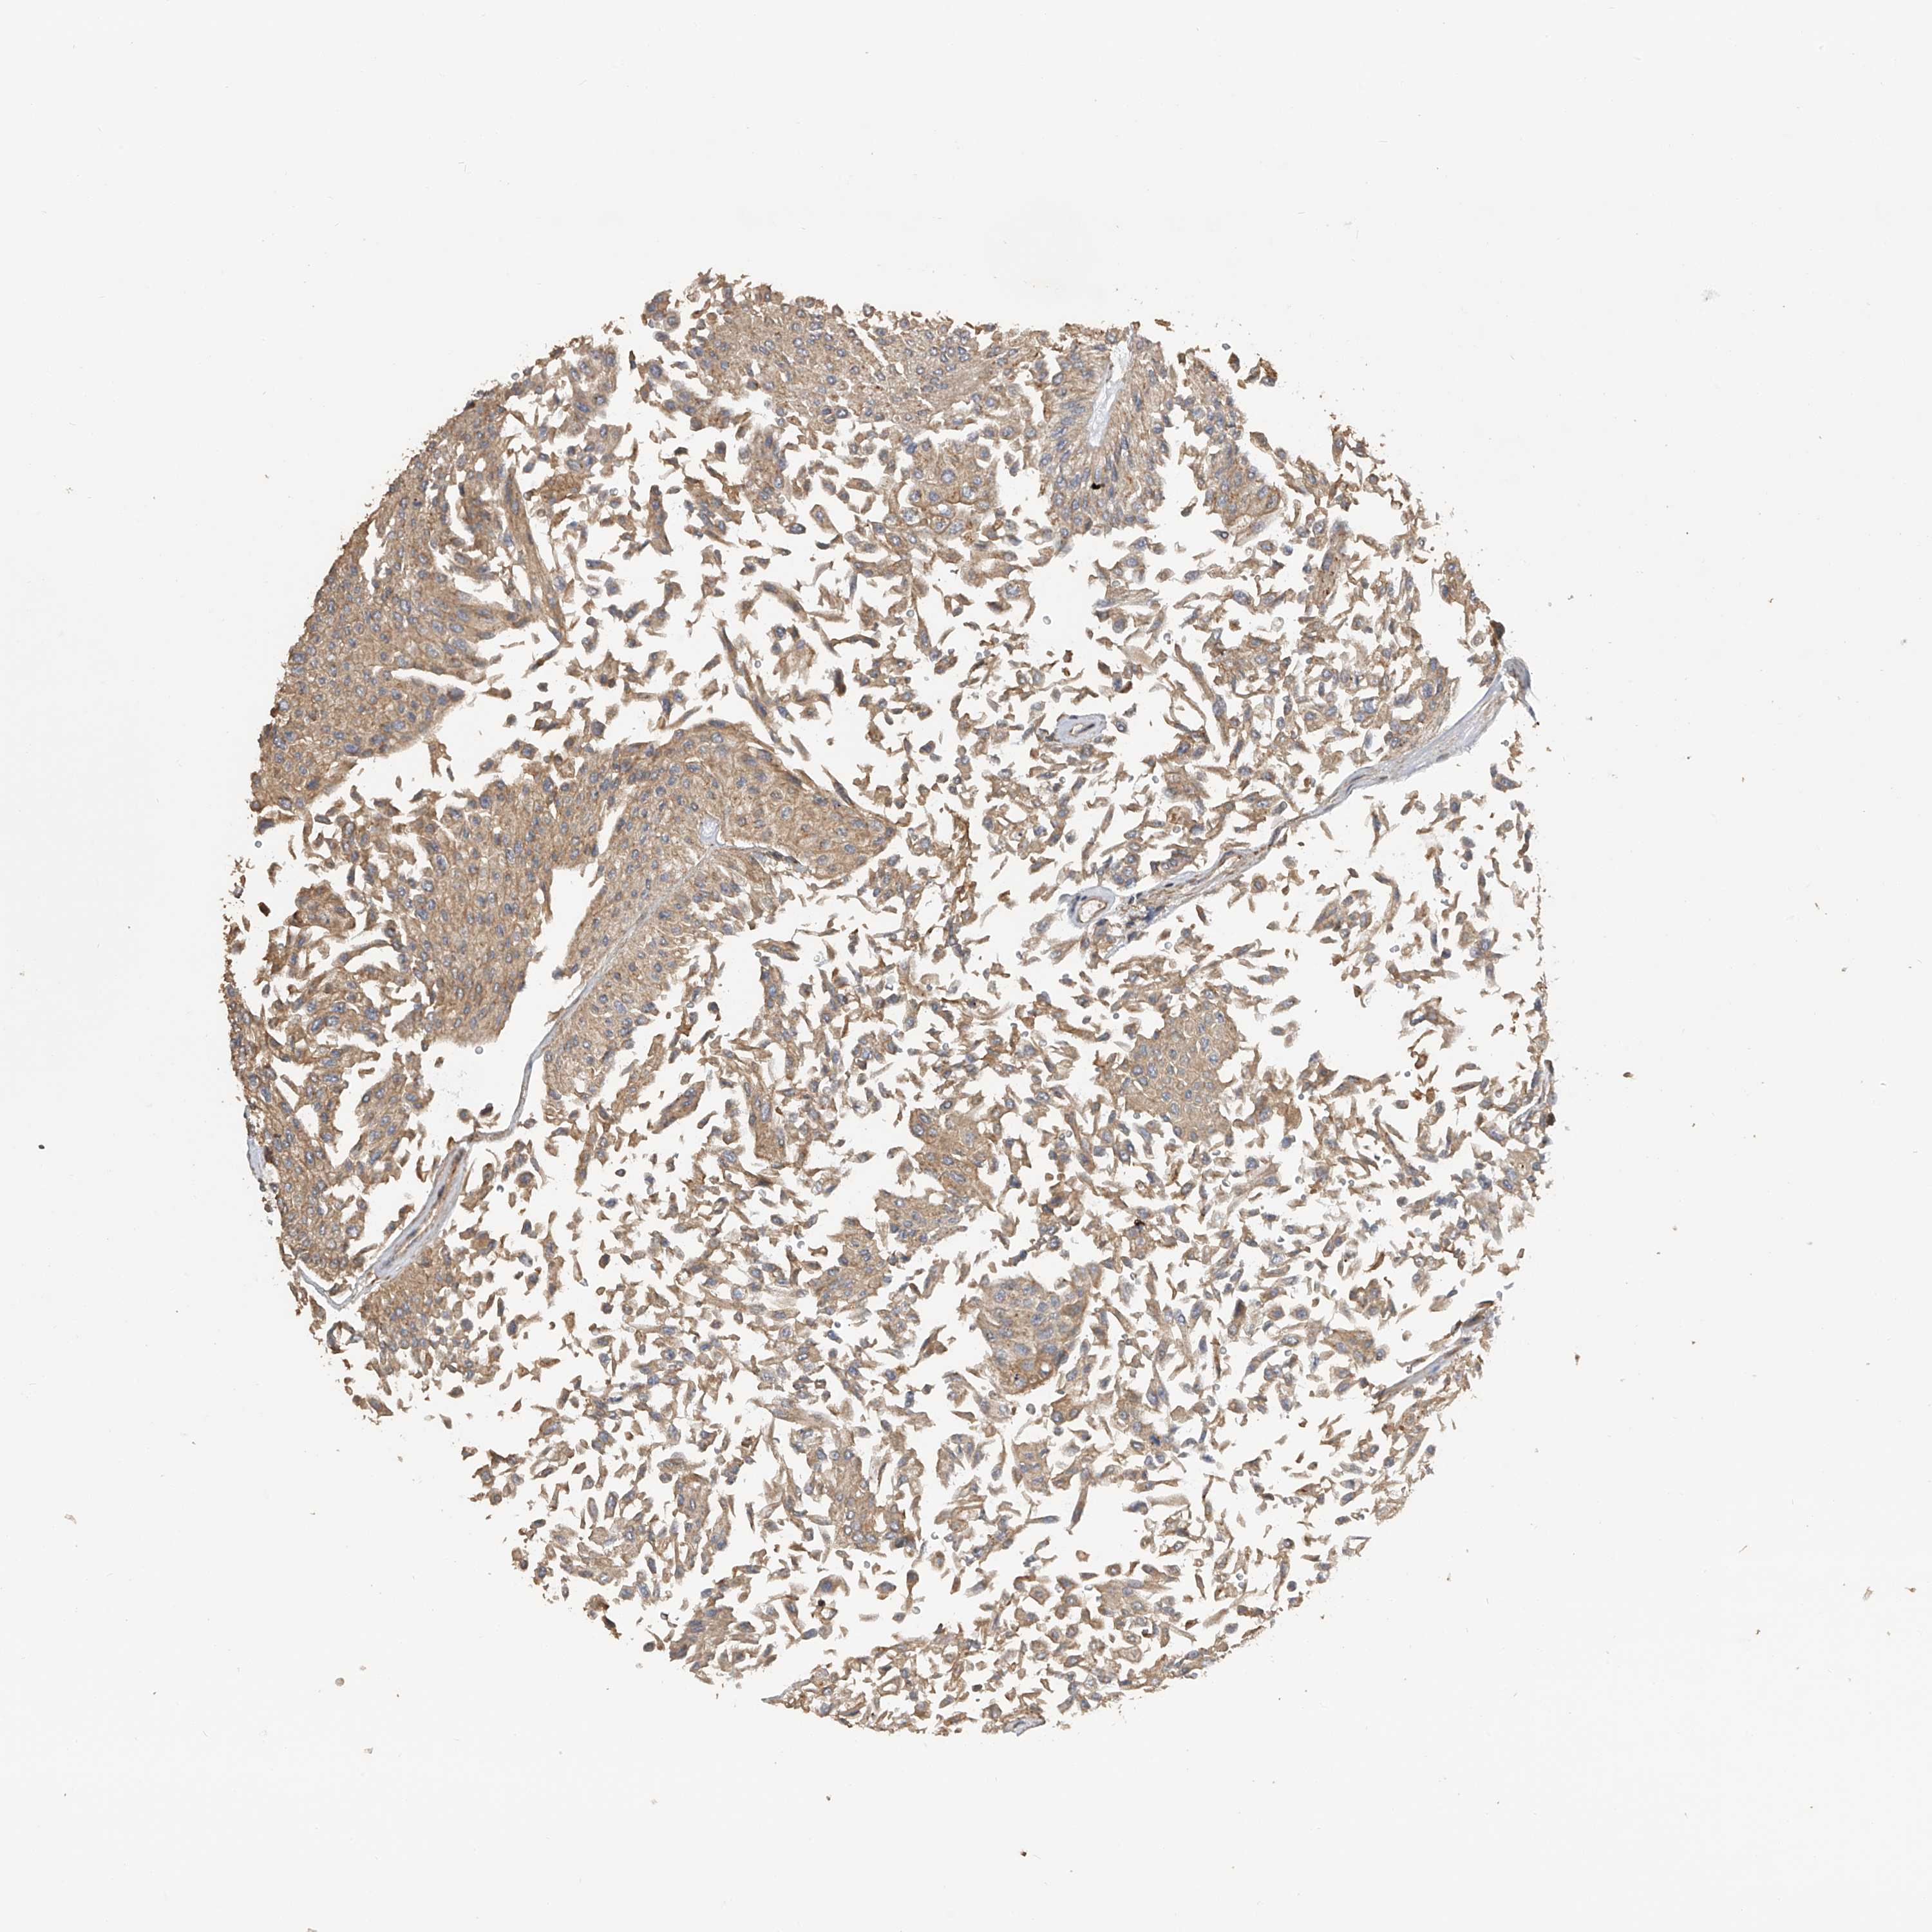

UROTHELIAL CANCER - Protein expressioni

A mouse-over function shows sample information and annotation data. Click on an image to view it in a full screen mode. Samples can be filtered based on level of antibody staining by selecting one or several of the following categories: high, medium, low and not detected. The assay and annotation is described here.

Note that samples used for immunohistochemistry by the Human Protein Atlas do not correspond to samples in the TCGA dataset.

Antibody stainingi

Antibody staining in the annotated cell types in the current human tissue is reported as not detected, low, medium, or high, based on conventional immunohistochemistry profiling in selected tissues. This score is based on the combination of the staining intensity and fraction of stained cells.

Each image is clickable and will lead to virtual microscopy that enables deeper exploration of all samples and also displays staining intensity scores, fraction scores and subcellular localization as well as patient and tissue information for each sample.

Antibody HPA029412

Antibody CAB034366

Staining

High

Medium

Low

Not detected

Intensity

Strong

Moderate

Weak

Negative

Quantity

>75%

75%-25%

<25%

None

Location

Nuclear

Cytoplasmic/membranous

Cytoplasmic/membranous,nuclear

Urothelial carcinoma, Low grade

Urothelial carcinoma, High grade